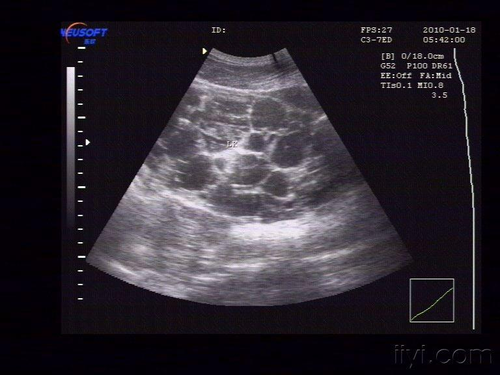

多囊肾是一种先天性的具有遗传机制的疾病,这种疾病也是一种良性疾病,但其会随着时间的推移而逐渐的变大,最后影响到肾脏功能,所以还是需要得到重视。一般情况下,肾脏上的囊肿超过0.5厘米,能够在彩超上表现出来。对于多囊肾,目前来说没有很好的药物能够彻底治愈,一般只是用药物来控制其增长以及预防其并发症的出现。这类病症虽然具有遗传性,但对于孩子来说,不是100%都会遗传。